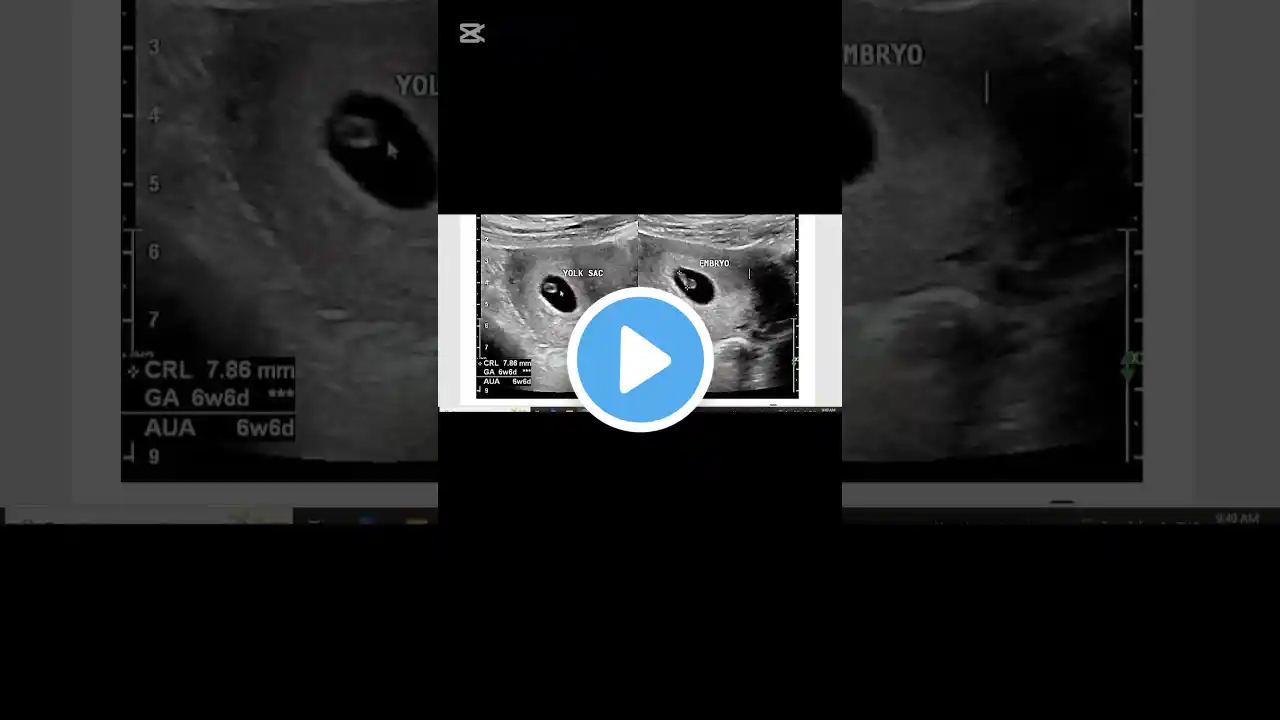

Yolk sac and fetal pole not seen meaning in hindi | Empty gestational sac